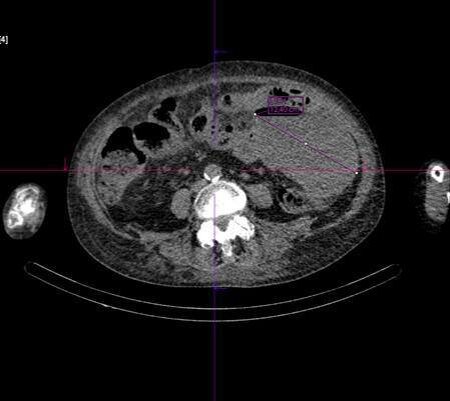

После планового обследования в Радиологическом центре Медгорода выяснилось, что ранее обнаруженная опухоль сигмовидной кишки привела к образованию крупного абсцесса. Без срочной операции ситуация грозила тяжелым перитонитом и смертью. Врачи оперативно вызвали скорую помощь, доставившую пациентку в областную клиническую больницу №1, где ей сделали операцию. Благодаря согласованным действиям медиков состояние женщины стабилизировалось, открыв перспективу полного выздоровления.

После планового обследования в Радиологическом центре Медгорода выяснилось, что ранее обнаруженная опухоль сигмовидной кишки привела к образованию крупного абсцесса. Без срочной операции ситуация грозила тяжелым перитонитом и смертью.

Врачи оперативно вызвали скорую помощь, доставившую пациентку в областную клиническую больницу №1, где ей сделали операцию. Благодаря согласованным действиям медиков состояние женщины стабилизировалось, открыв перспективу полного выздоровления.